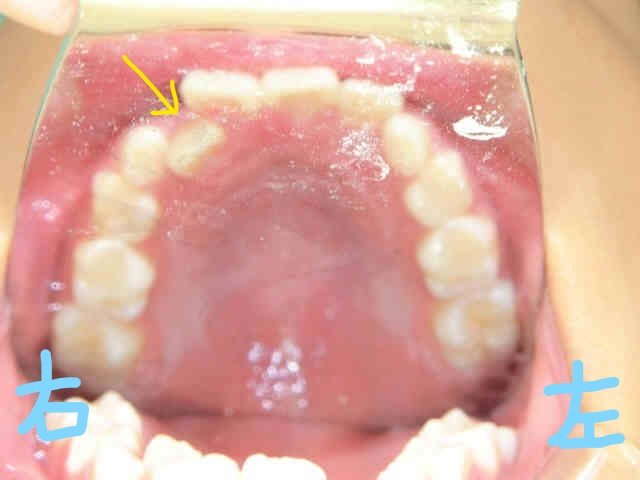

初診時の写真(左上:正面、右上:下から見上げた正面)では、右上前歯(黄色矢印)が内側に入り込み、下顎前歯(赤波線部)には叢生(歯列の重なり=ガタガタの歯並び)が見られました。

さらに上下顎の咬合面の写真からも、上顎前歯の内側移動と、下顎前歯の叢生が確認されます。

このまま成長を迎えた場合、叢生が進行し、犬歯が歯列外に萌出する「八重歯」の状態になる可能性がありました。

このようなケースで、すべての永久歯が生えそろってから矯正を開始すると、歯を並べるスペースが足りず、抜歯が必要な「抜歯矯正」となる可能性が高まります。

みらい歯科クリニックでは、早期(小学校2年生・7~8歳ごろ)に矯正を始めることで、抜歯を回避できる可能性がある「混合歯列期」の治療を推奨しています。